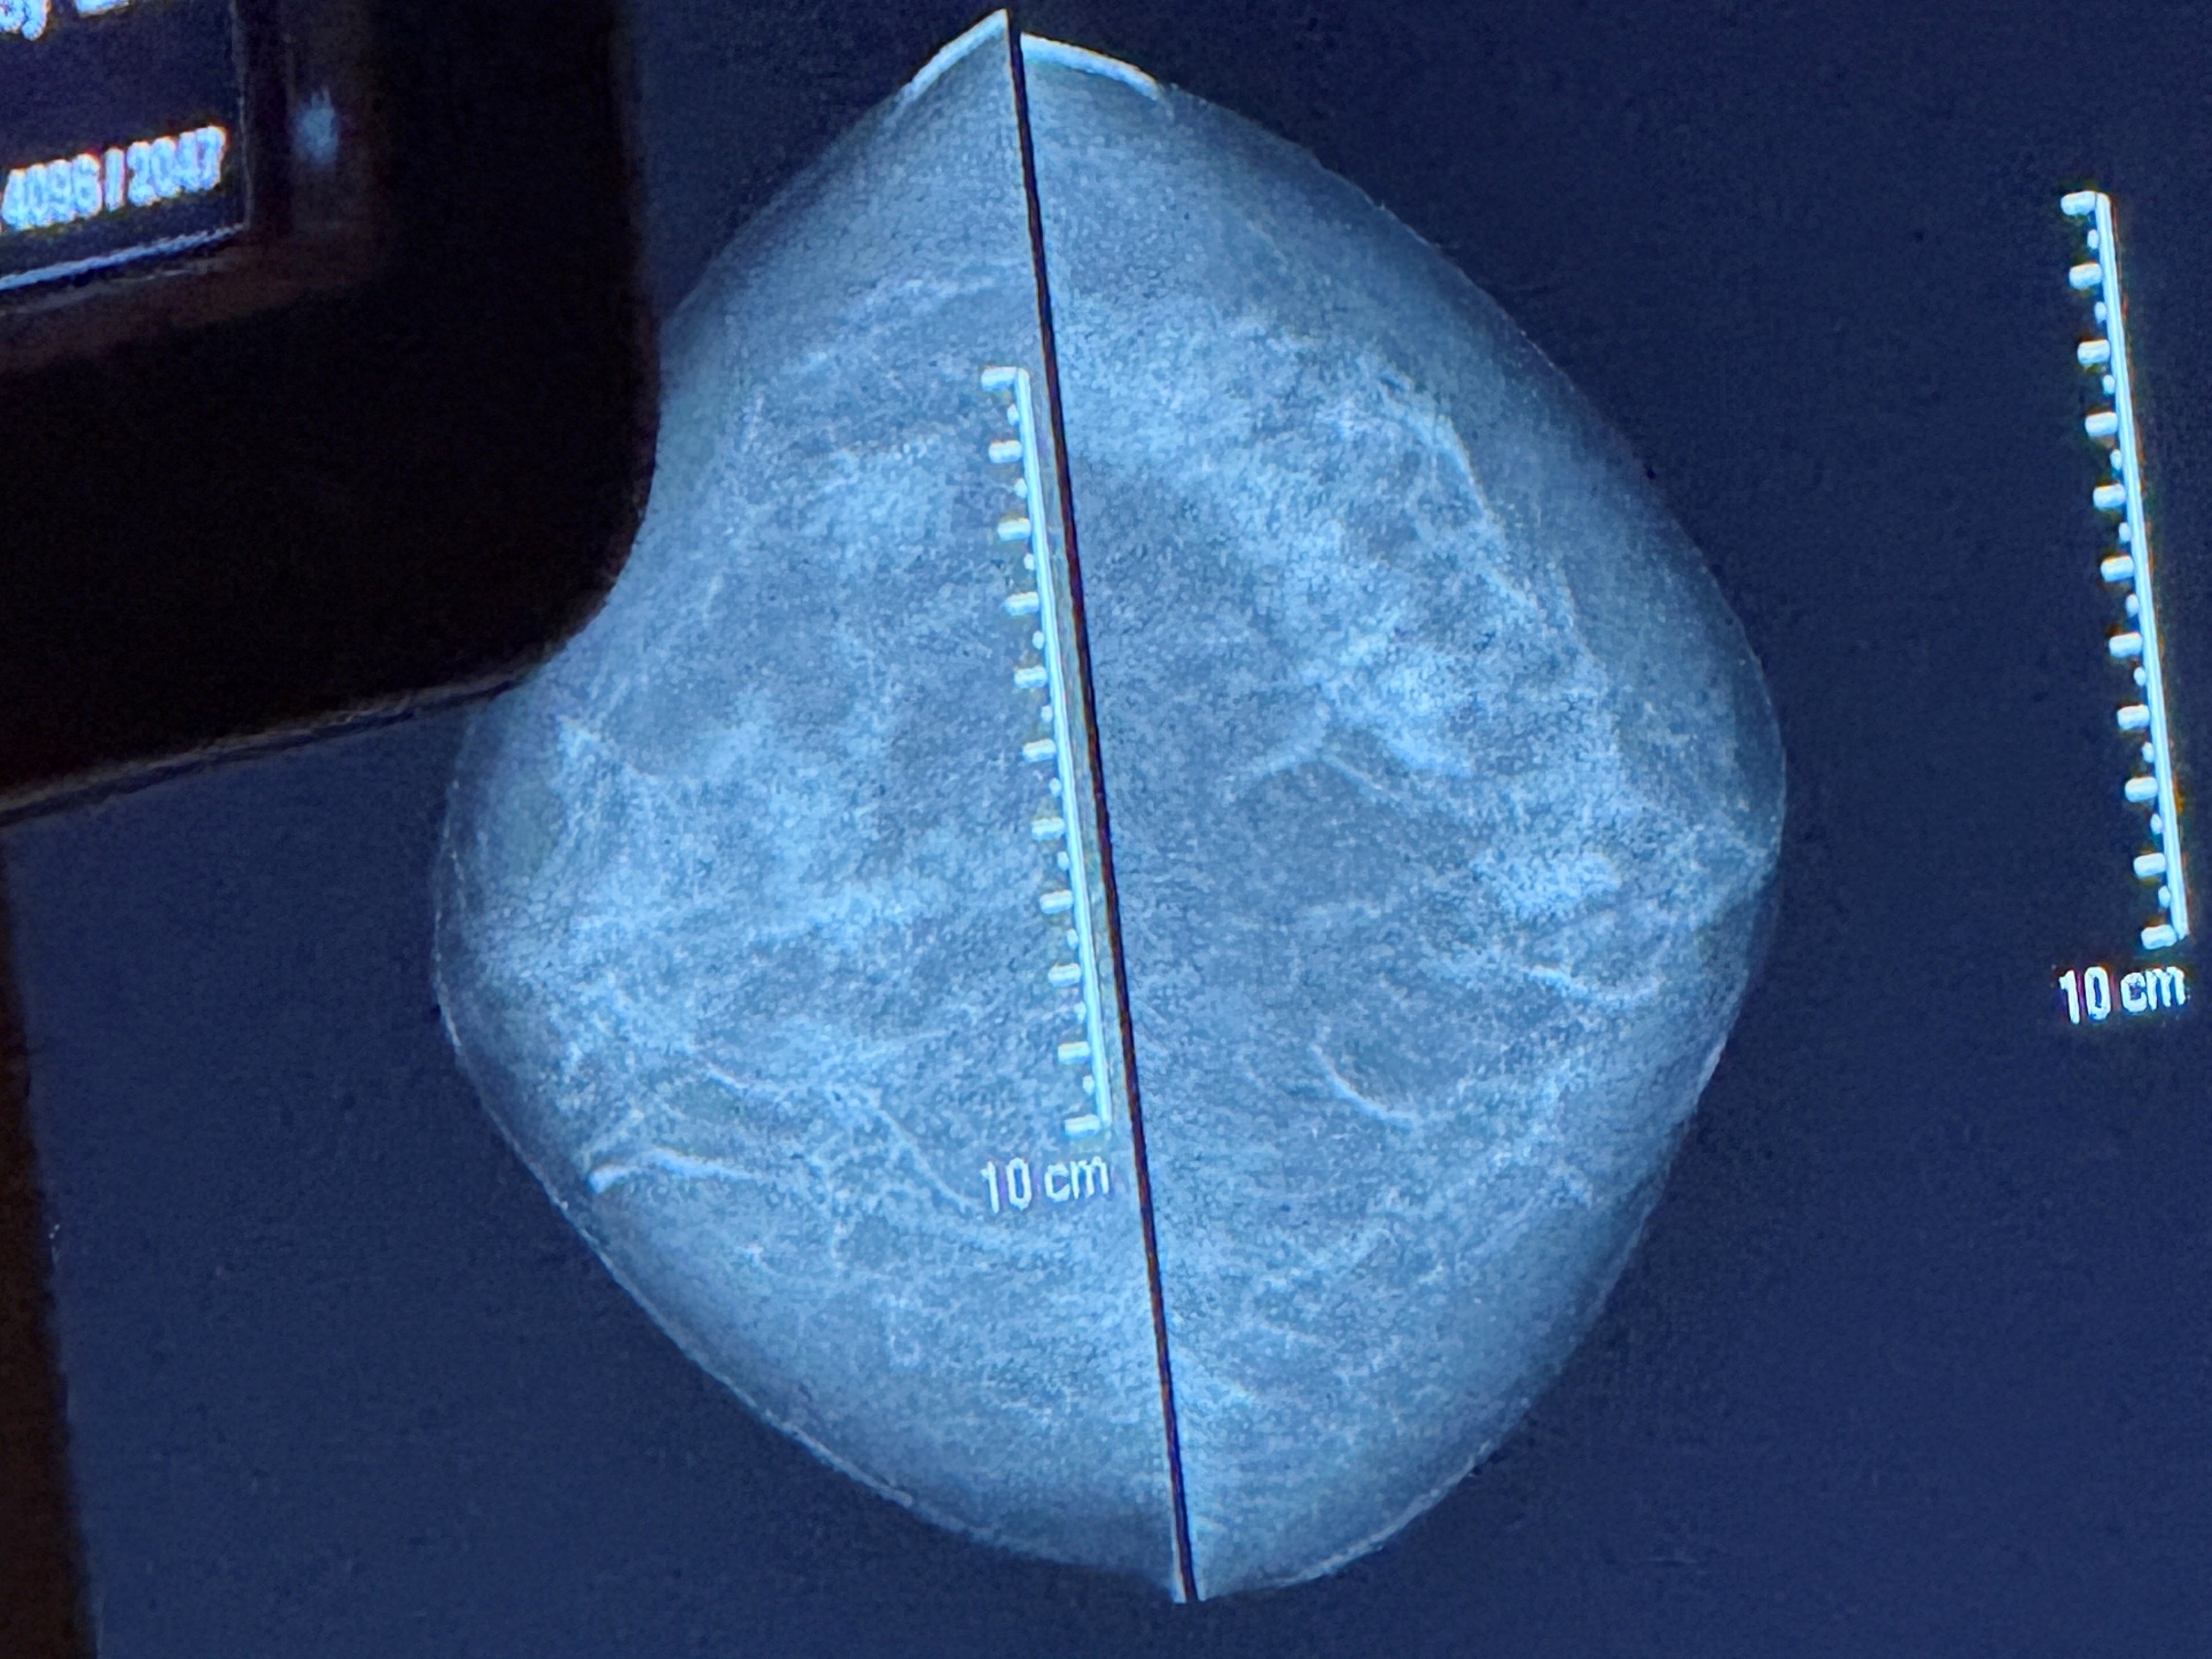

Screeningen inngår i det nasjonale mammografiprogrammet som tilbyr mammografi annethvert år til kvinner mellom 50 og 70 år. Målet er å oppdage brystkreft på et tidlig stadium og før sykdommen gir symptomer, for å øke sjansen for vellykket behandling.

I Norge er brystkreft den vanligste kreftformen blant kvinner, og omtrent 3.500 kvinner får diagnosen hvert år. Mammografiscreening har dokumentert effekt, og studier viser at programmet kan redusere dødeligheten i brystkreft med opptil 20 prosent blant kvinner som deltar regelmessig.

– Dette er en undersøkelse mange gruer seg for, og dere kommer svært tett på disse kvinnene med helt nødvendig berøring og fysisk posisjonering av brystene i apparatet. Det er fint å se den tryggheten og roen dere utviser, med stor empati og respekt, sier Alice Beathe.